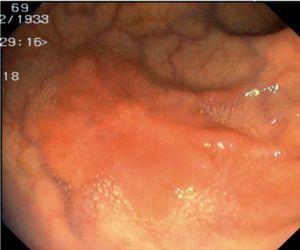

Fig. 3. Examples of flat lesions with conventional examination and after the application of indigo carmine 0.2-0.5%. a, b) Small flat adenoma, 3 mm in size. c, d) Large flat adenoma, 15 mm in size. e, f) Completely flat lesion (IIb in the Japanese classification). g, h) Depressed lesion, 3 mm in size) (IIc in the Japanese classification). I, J) Depressed lesion, 7 mm in size, histopathological study revealed submucosally invasive cancer (traditionally IIc in the Japanese classification, although recently such depressed lesions with a distinct central protrusion indicating submucosal invasion are termed IIc + Is). k, l) Flat elevated lesion with central depression, 10 mm in size, corresponding to a submucosally invasive cancer (IIa + IIc in the Japanese classification).